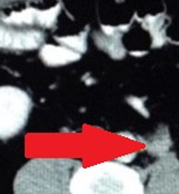

CT κοιλίας. Διάβρωση/μετανάστευση του πλέγματος εντός του ορθού (Ευγενική παραχώρηση Dr. V. Penopoulos)